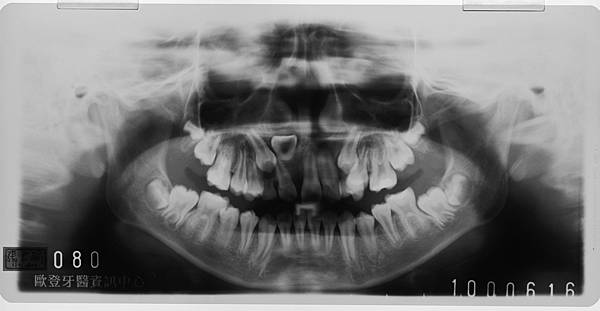

【大紀元1月20日報導】(中央社記者郝雪卿台中市20日電)彰化縣一名6歲女童換牙時,2顆正中門牙只長出右邊1顆,經X光檢查發現門牙逆向生長,擔心咬合不正影響發音,中山醫學大學附設醫院矯正一年後,終於拉回正常位置。

中山醫學大學口腔醫學研究中心兒童牙科蔡尚宏今天表示,這名女童在換牙時因為左邊門牙遲遲不長,家長帶來看診,經安排照X光片後發現,原本應該向下生長的門牙竟逆向生長,出現像牛角般的怪異形狀,經過一年矯正後,終於將長歪的門牙拉回正常位置。